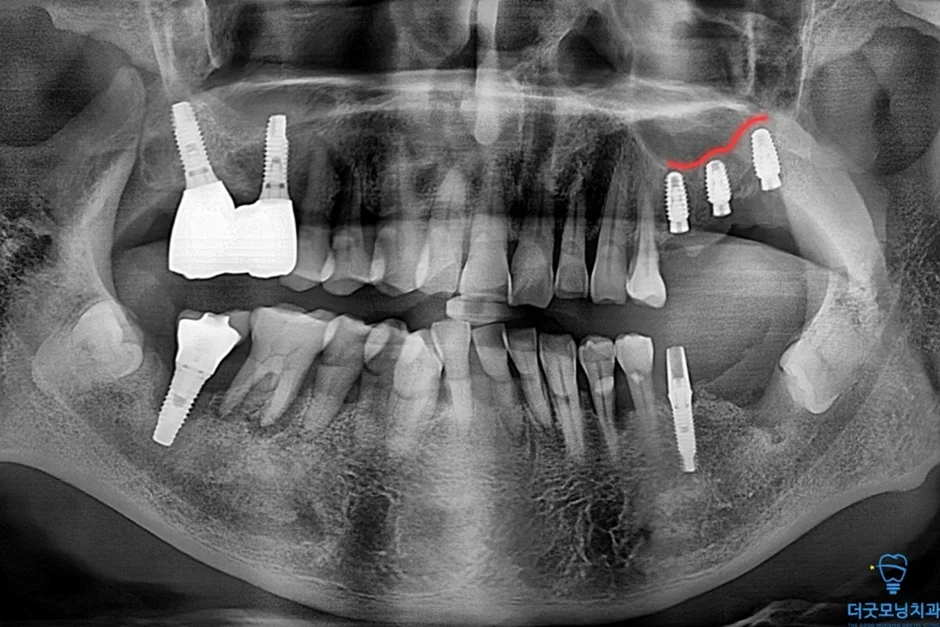

■ 보철 마무리

양쪽 임플란트 식립이 완료된 후 보철 준비를 거쳐 최종 보철까지 마무리하였습니다.

오늘 소개해 드린 증례는 임플란트 재수술 + 치조정 접근 상악동 거상술 + 어금니 전체 임플란트를 수면마취를 통해 편안하게 해결해 드린 케이스입니다.